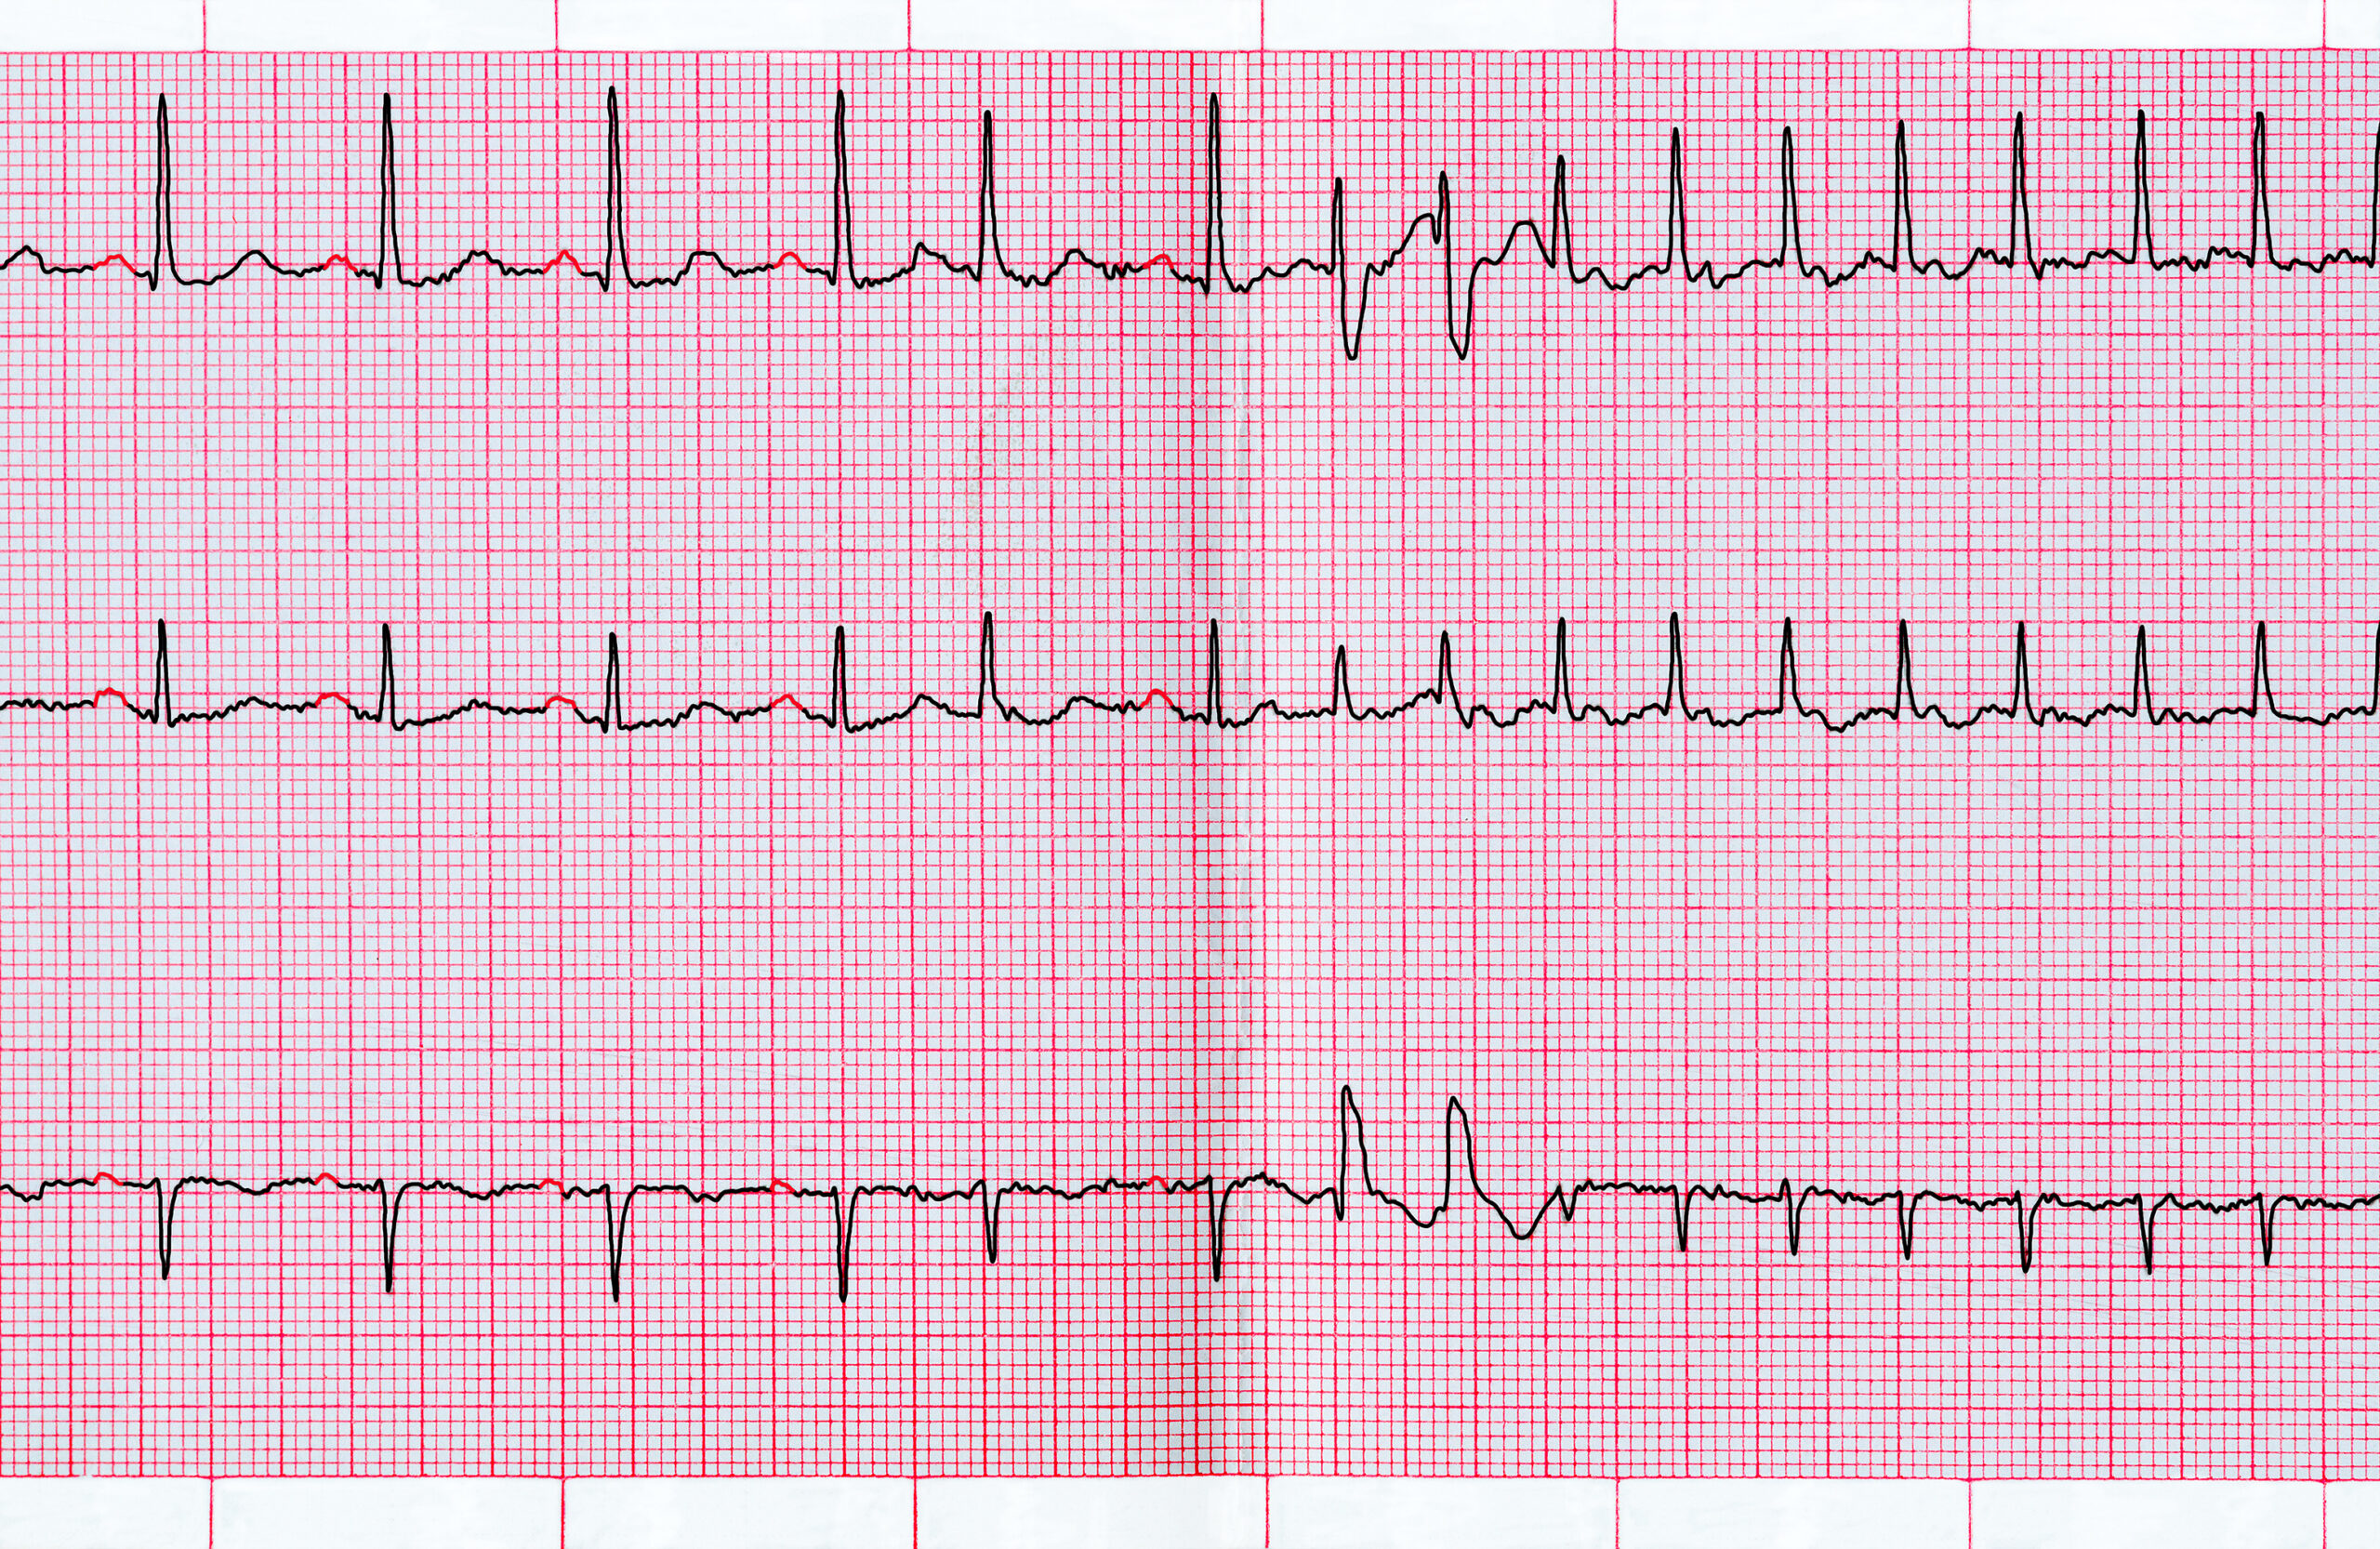

Asymptomatic patients with high grade premature ventricular contractions (PVCs) in the recovery phase of the stress test ...

Ambulatory electrocardiographic monitors (AECG) are widely utilized in the detection of clinically significant ...